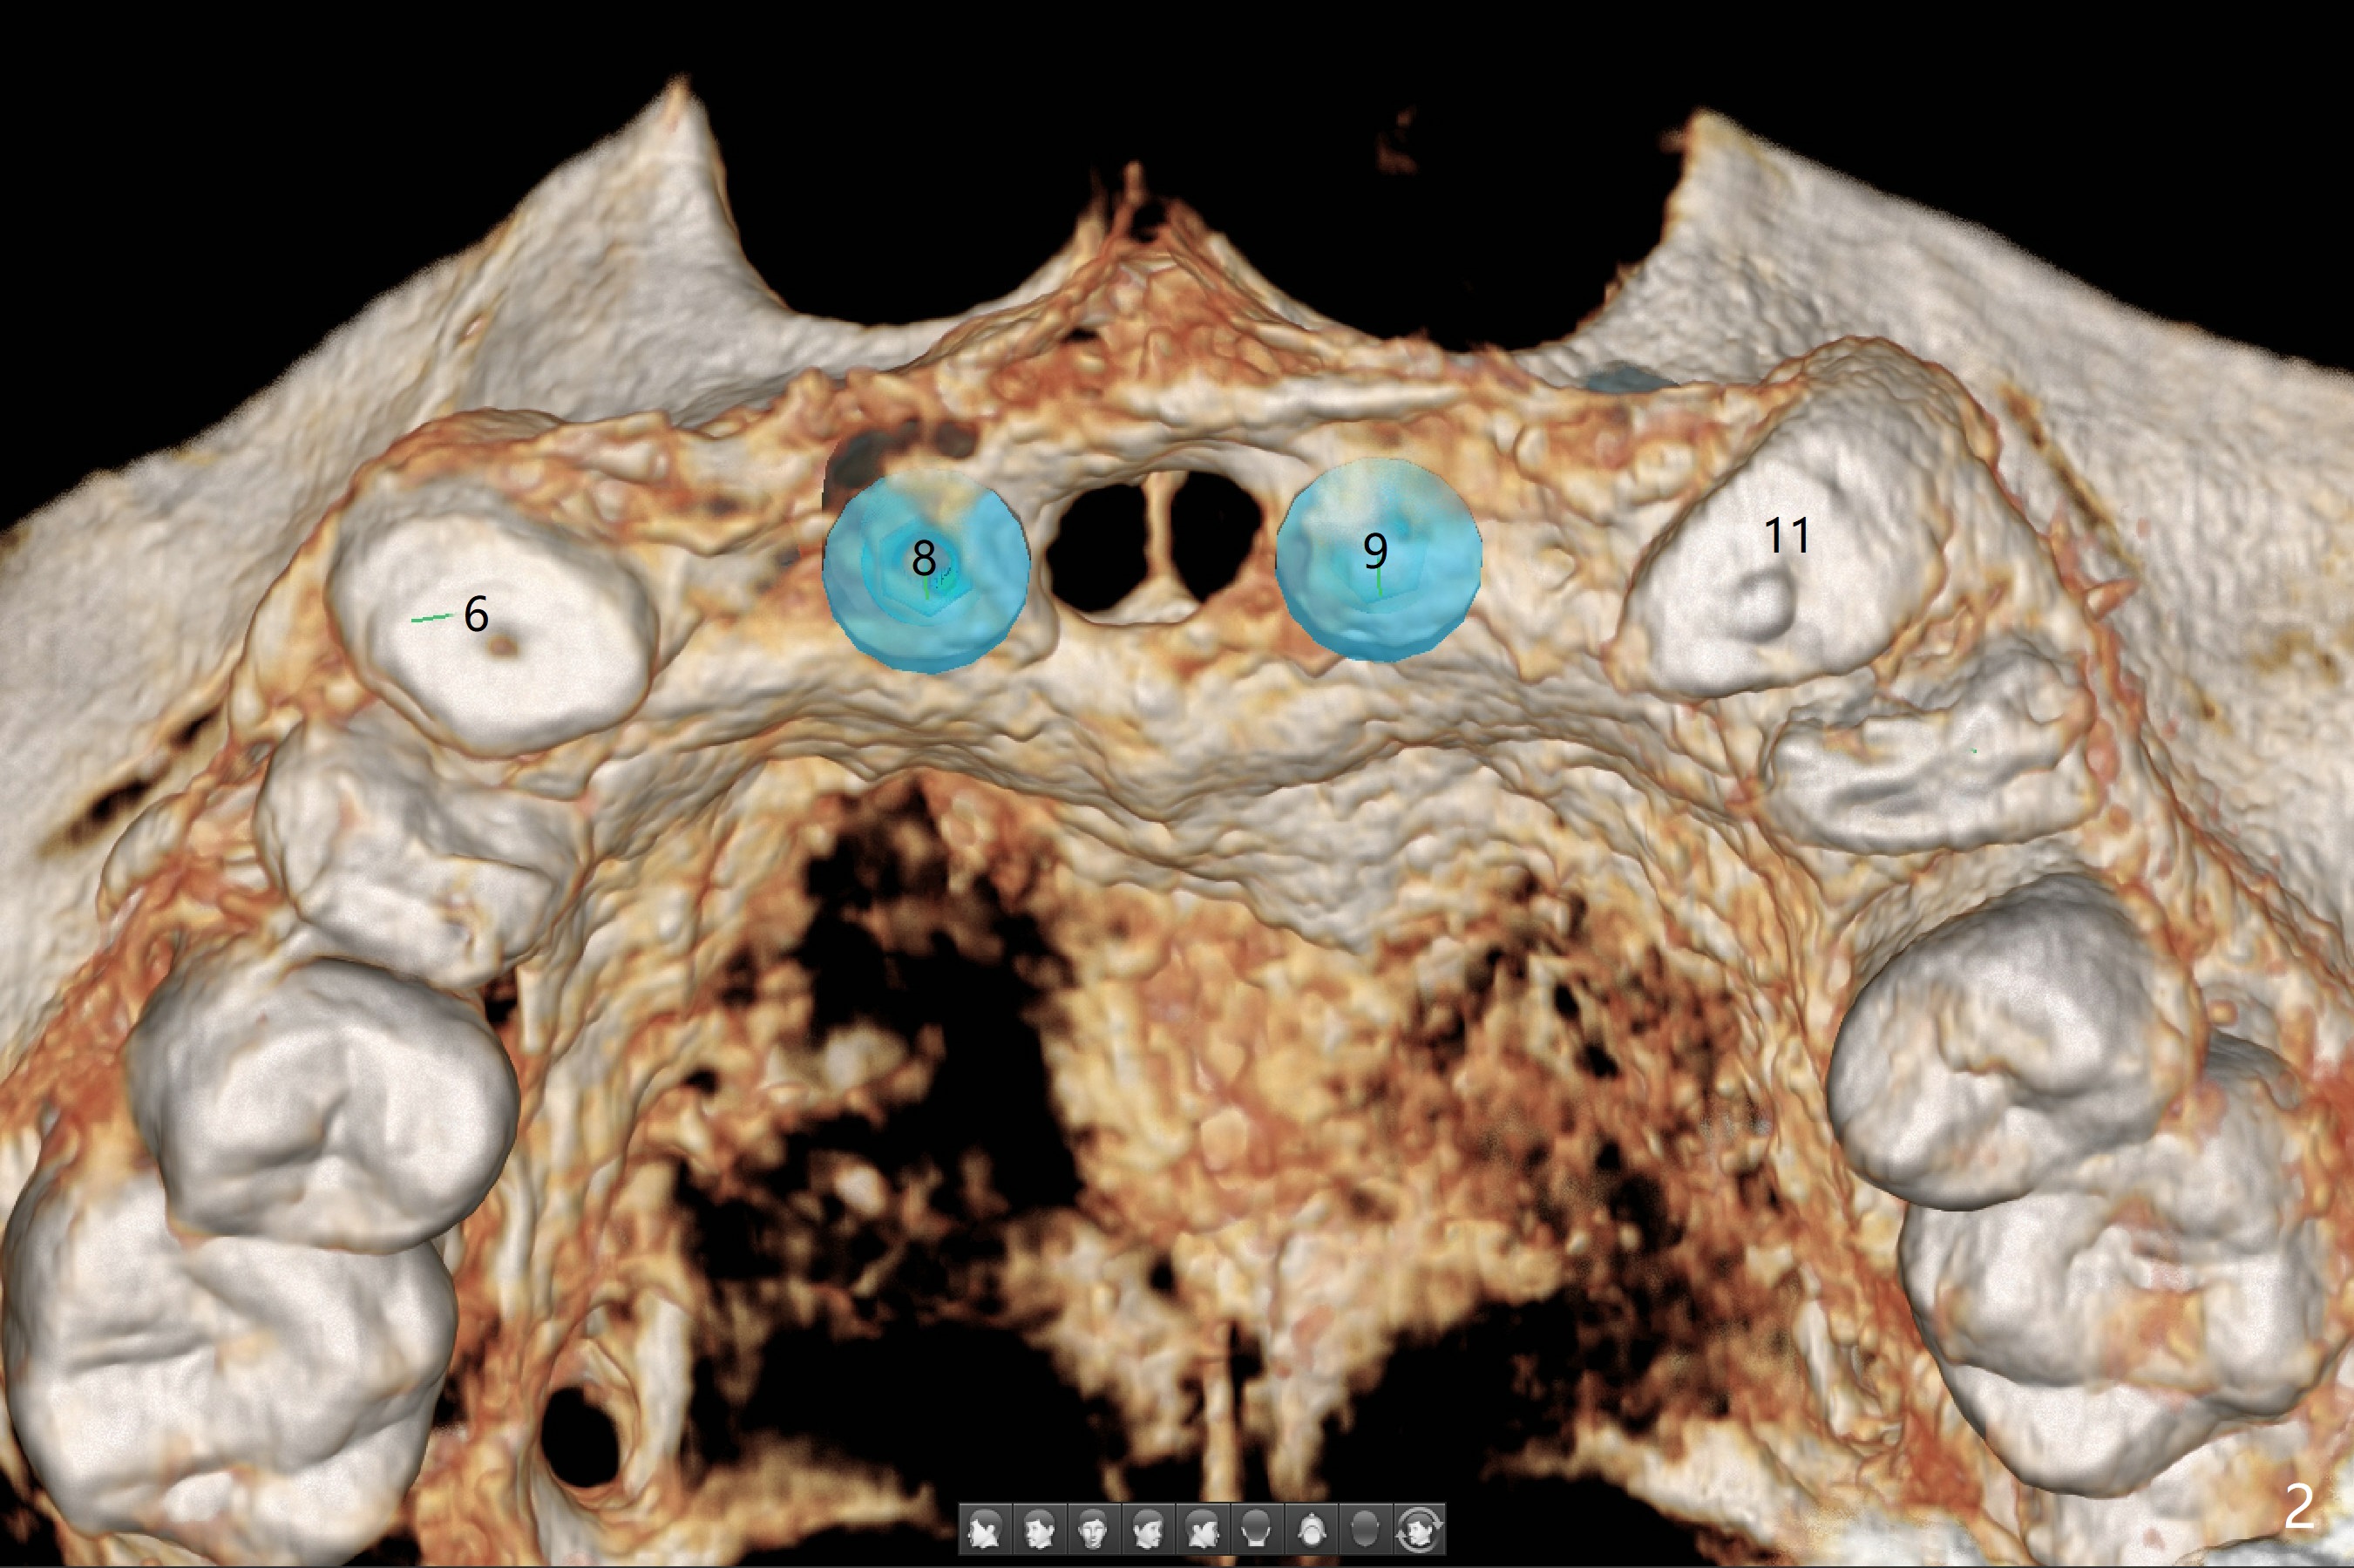

A 78-year-old man's 8 unit FPD dislodges (#5-12, Fig.1). Three of 4 abutments seem to be non-salvageable (#6,11,12 fractured equigingival, extraction, immediate implants). For restoration, implant will be placed at #8 and 9 as well. Implant FPDs will be fabricated at #6-8 and 9-11 (Fig.2) with #5 (with build up or prefabricated post) and 12 single unit crowns to better withstand deep overbite and overjet. After discussion with lab, a major change will be implants to be placed at #7 and 10 instead of #8 and 9 (narrow ridge). The implant at #7 will be a 1-piece (3 mm in diameter), whereas the rest 2-piece (3.5 mm). The abutment of IS 1-piece implant is 10 mm in length, while that of DIO's 5 mm. The former will be used if the vertical space is sufficient.